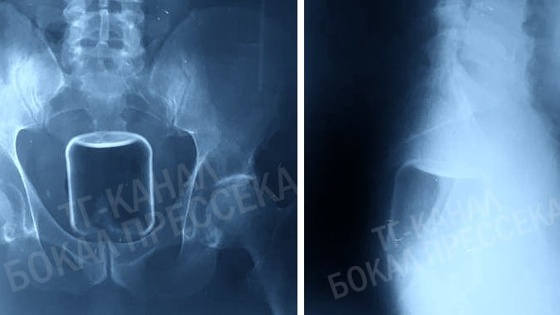

Медики достали из организма жителя Нижегородской области банку объемом в 0,5 литра. Об этом рассказал редактор «Стационар-пресс» Алексей Никонов.

Банка застряла в кишечнике мужчины, и на помощь ему пришли хирурги. Им пришлось действовать очень аккуратно, чтобы не допустить появления осколков, которые могли повредить слизистую. Операция прошла успешно.